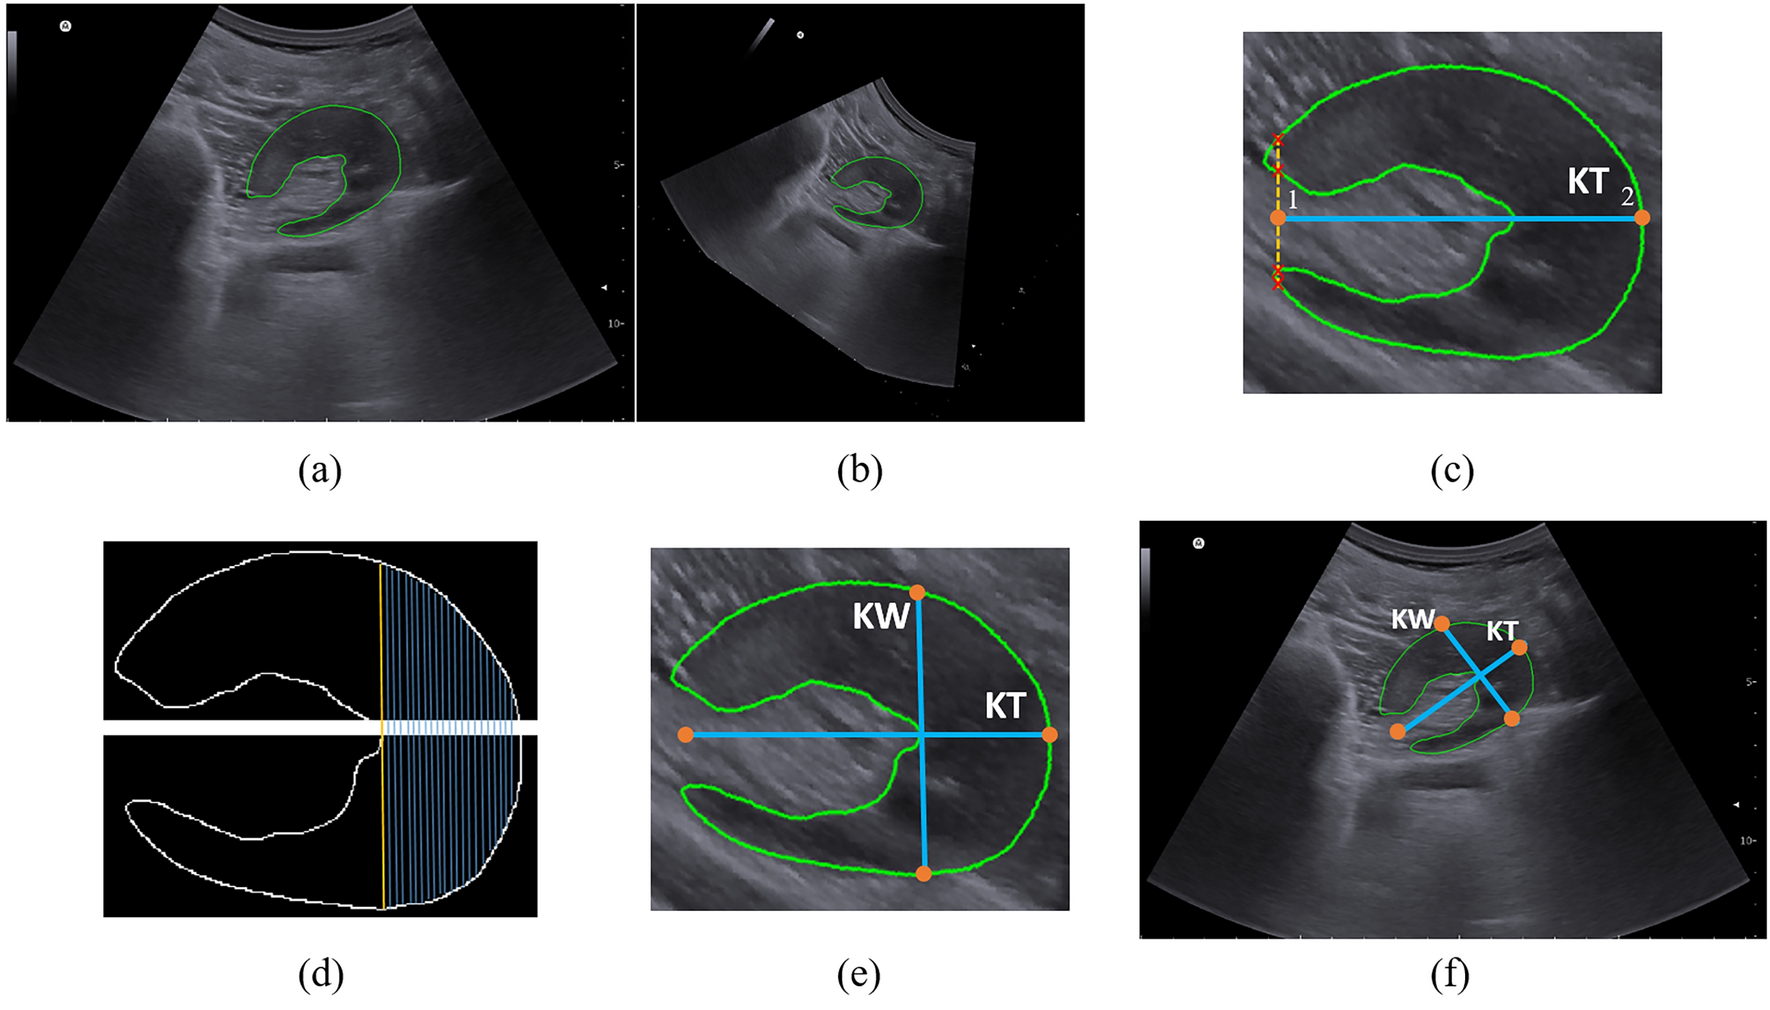

Figure 3

Post-processing of axial view image. (a) Segmentation of axial image, (b) rotation of the image to make it horizontal, (c) estimating kidney thickness (KT) by finding two terminal points, (d) separation of upper and lower parts of the mask and finding the longest distance, (e) kidney width (KW) and KT, and (f) KW and KT in the original image.